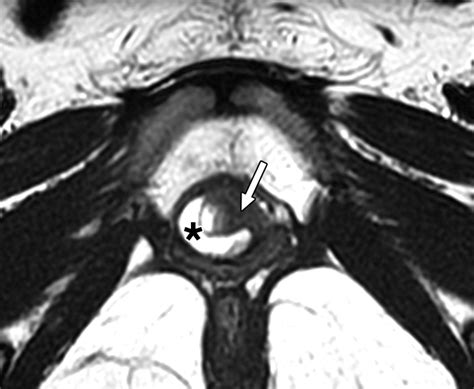

MRI (Magnetic Resonance Imaging) The gold standard for visualizing the size and location of the diverticulum.